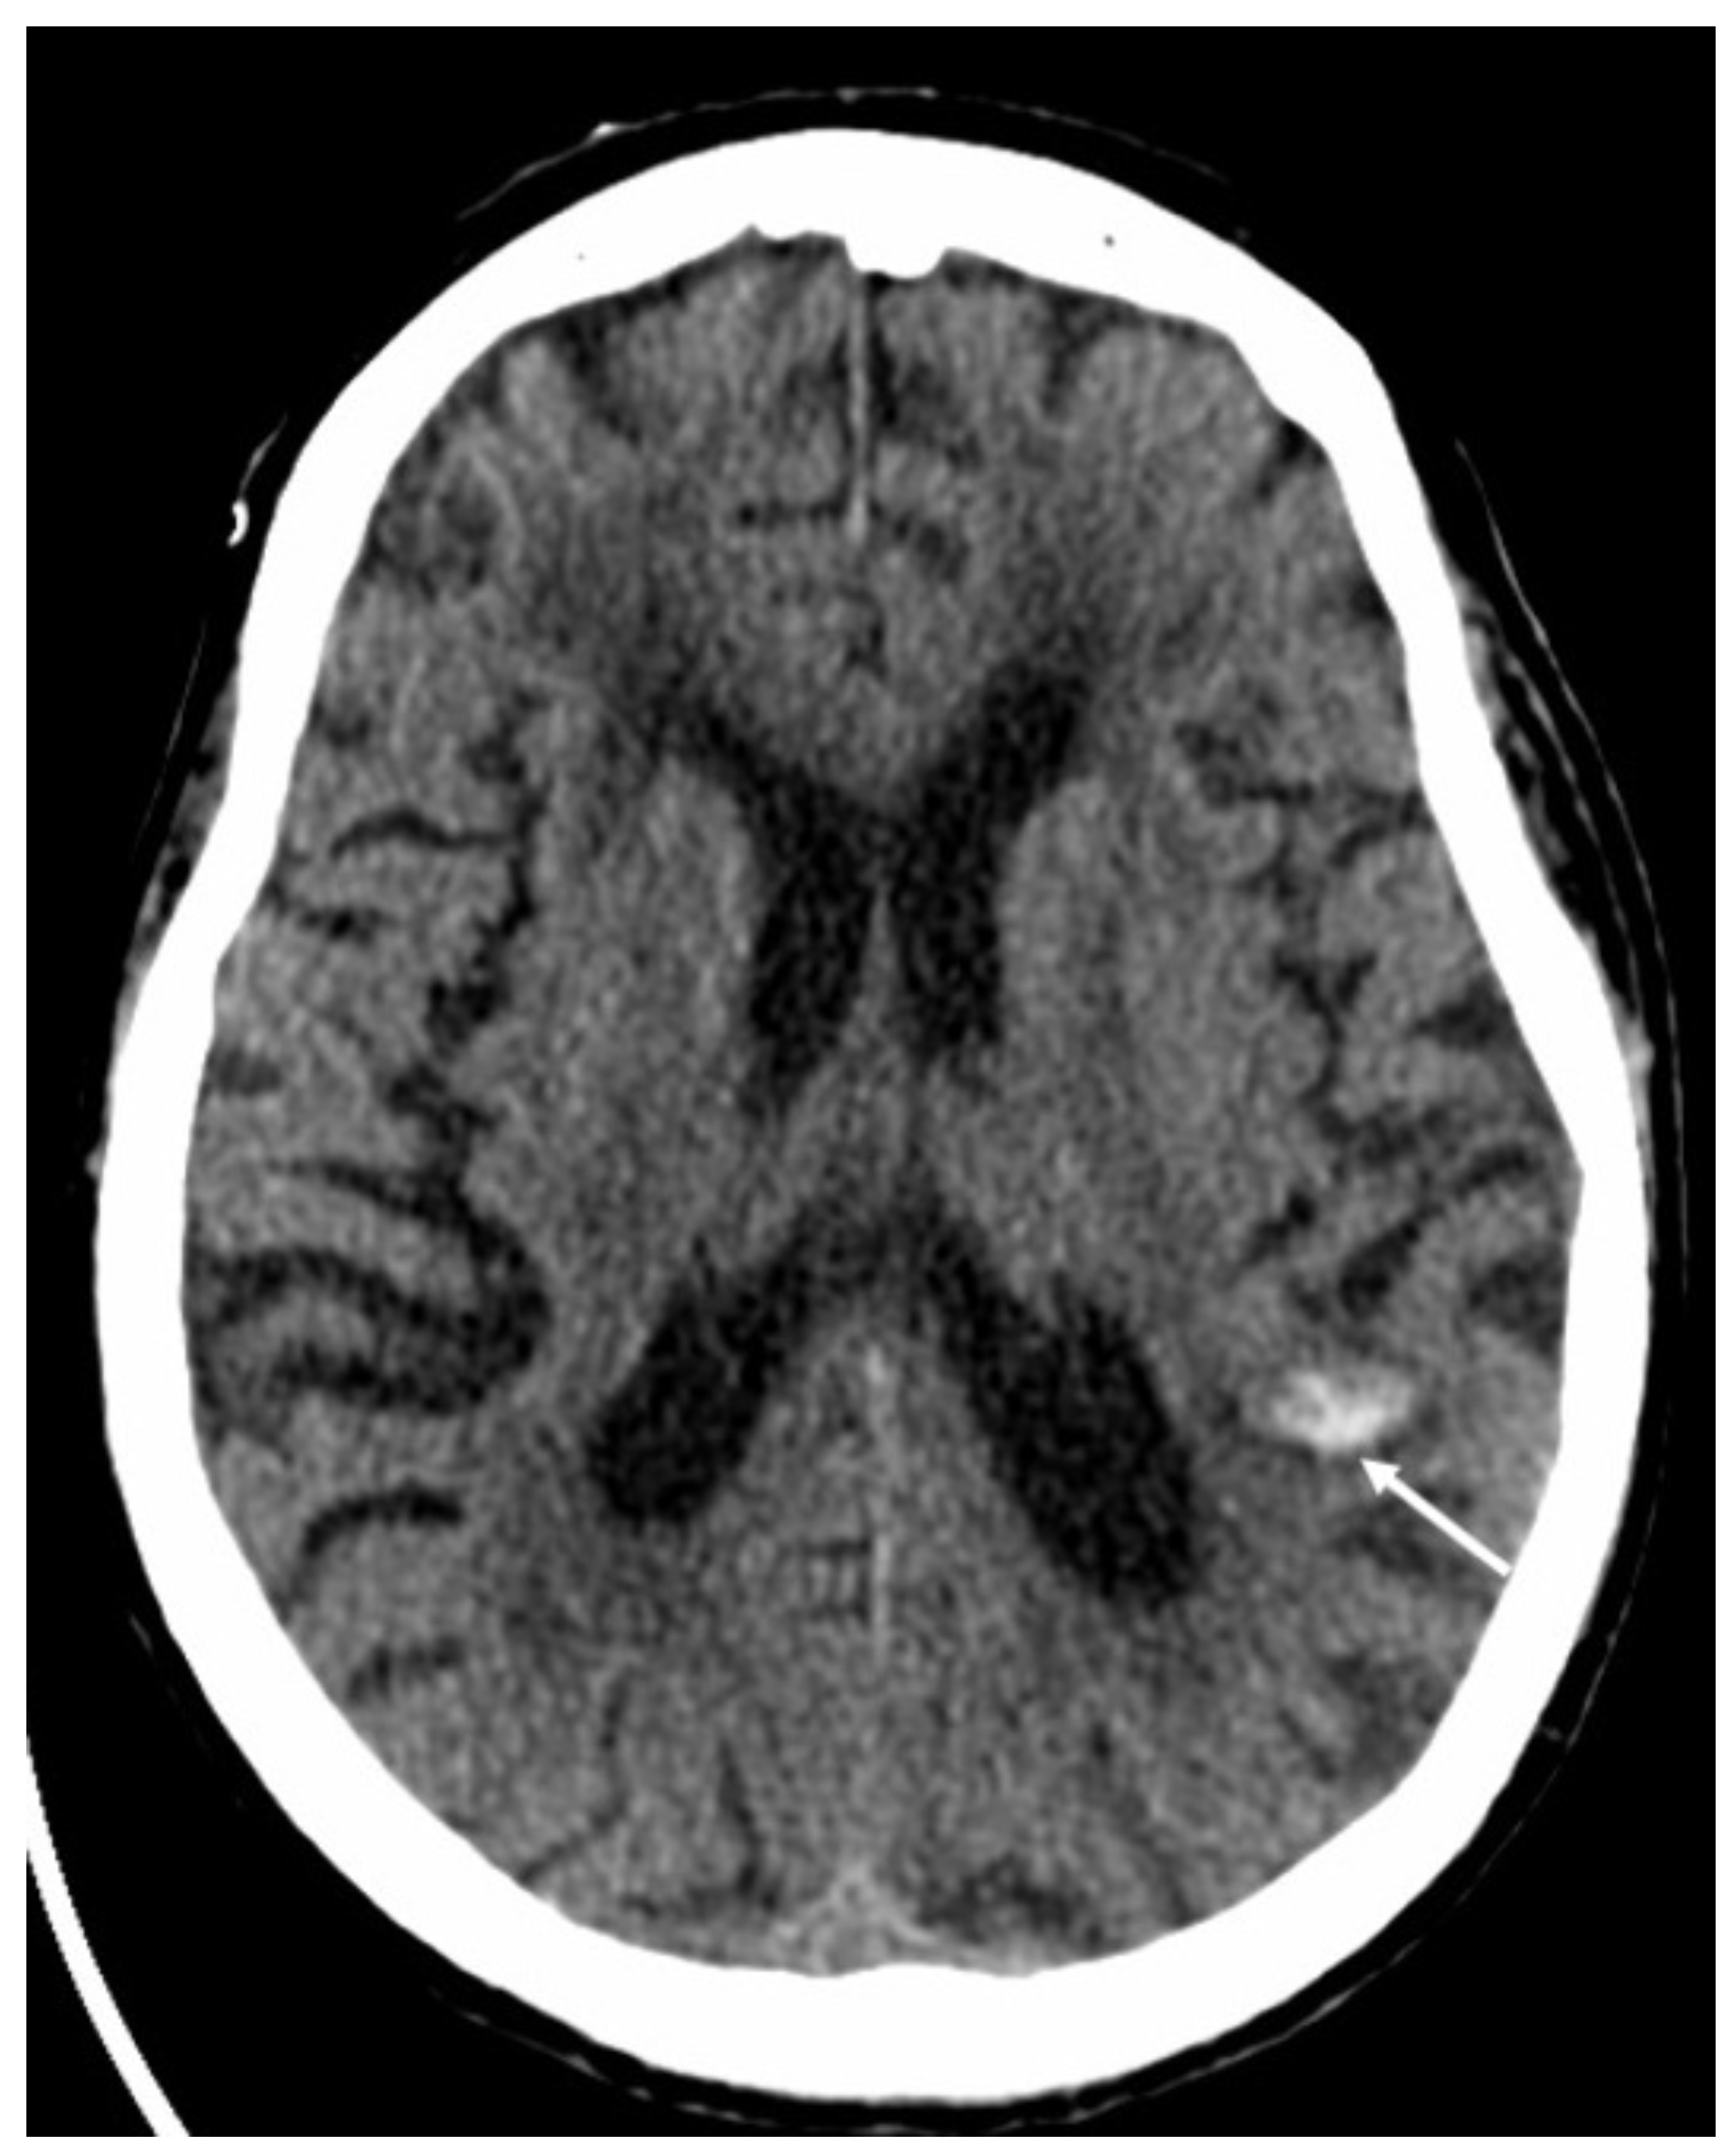

Figure 17.

Axial computed tomography shows a small hemorrhage in the subcortical region of the left parietal region (arrow) in a patient with varicella zoster virus encephalitis.